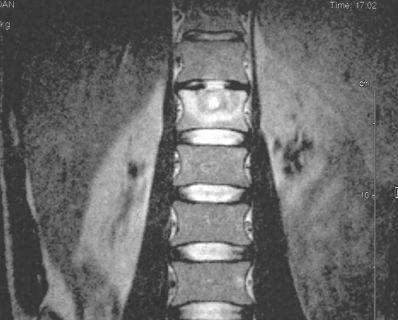

Инструментальные методы диагностики включают рентгенографию, компьютерную и магнитно-резонансную томографию, которые обнаруживают разрушение одного или нескольких позвонков. Рентгенологические признаки туберкулезного спондилита:

- деформация замыкательных пластинок;

- сужение межпозвоночной щели вследствие разрушения межпозвонкового диска;

- узурация позвонков;

- очаговый остеопороз;

- клиновидная деформация позвонка;

- компрессионные переломы.